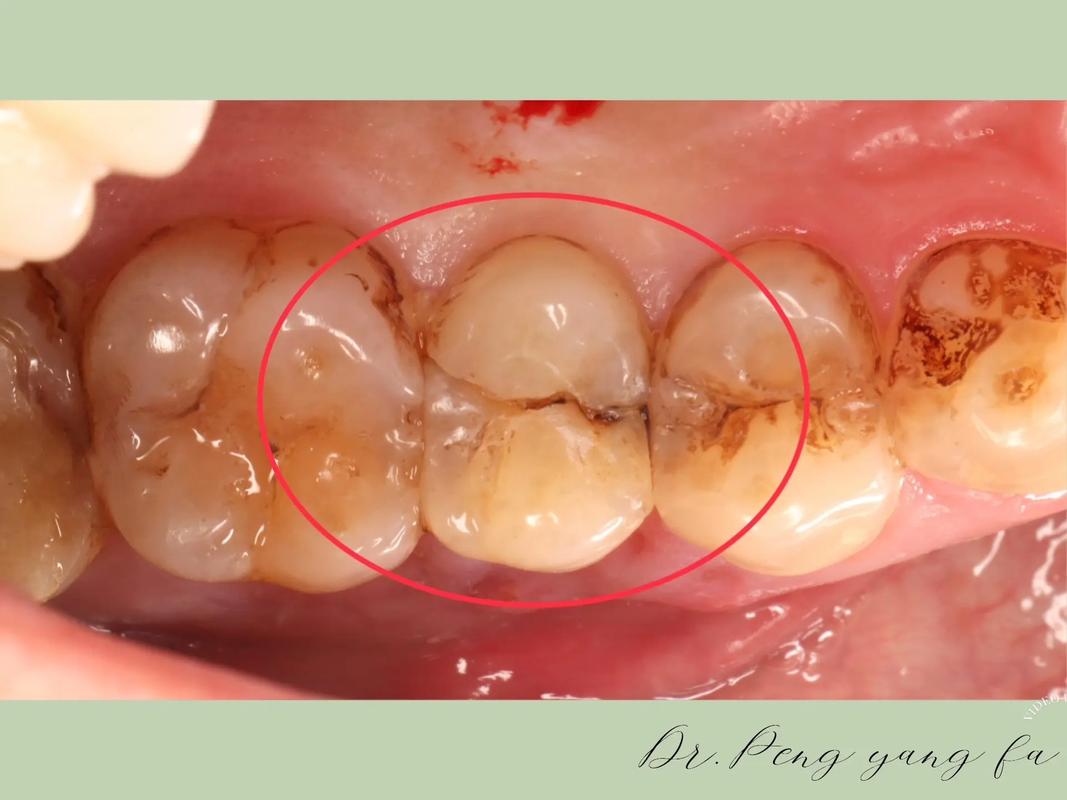

正畸过程中牙齿侧面裂的形成,首先与矫正力的施加密切相关,牙齿移动是通过牙槽骨改建实现的,若矫正力过大、移动速度过快,或牙根形态异常(如牙根短、弯曲)导致应力集中,牙体组织可能因承受超过其生理限度的力而产生裂纹,尤其是对于牙釉质发育不全、氟斑牙或四环素牙等牙体结构薄弱的牙齿,釉质本身脆性较高,正畸中更易出现裂纹,口腔卫生管理不当是重要诱因,正畸装置(如托槽、弓丝)易存留食物残渣,若清洁不到位,菌斑堆积会导致牙釉质脱矿,形成白垩色斑块,降低牙体强度,在咀嚼或外力作用下易裂,咬合异常(如个别牙齿早接触、夜磨牙)也可能导致牙侧面异常受力,长期反复的微小创伤会逐渐形成裂纹。

牙齿侧面裂的影响不容忽视,浅表裂纹可能仅表现为牙面粗糙,无自觉症状,但易色素沉着(如茶渍、烟渍),影响美观;深裂纹则可能引发牙齿敏感,遇冷热酸甜刺激时疼痛,若裂纹深及牙髓,还会导致牙髓炎,出现自发性疼痛、夜间痛等症状,严重时,裂纹可能造成牙齿折裂,甚至导致牙齿丧失,影响正畸效果及后续修复。